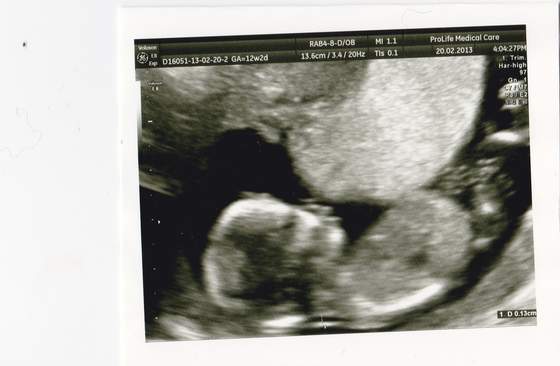

Ja dziś byłam na szybki podgląd mojego paproszka - i seruszko bije, ma 2,1 cm. Co mnie zmartwiło to to, że byłam już na USG dwa razy wcześniej. Wg USG dziecko było najpier jeden a potem dwa "dni starsze niż z OM a dziś dwa dni "młodsze" niż to wynika z OM... Czy to nie jest niepokojące?

Pamiętaj, że wiek z pomiarów zależy tylko i wyłącznie od tego jak gin zaznaczy te plusiki na obrazie płodu/zarodka ;-) Ponadto na wydruku z usg masz obok pomiaru (długość) i wieku ciąży jeszcze takie "widełki"

Zacytuję mój wydruk:

CRL 37,60mm 10w5d 10w1d-11w1d ---> i o to mi chodzi- wielkość dzidzi odpowiada wiekowi ciąży pomiędzy początkiem 11 i 12 tc. A jeszcze kiedyś na monitorze obok wyniku pomiaru widziałam, że się wyświetla +/- 3dni.

Więc spoko, najważniejsze, że serduszko bije